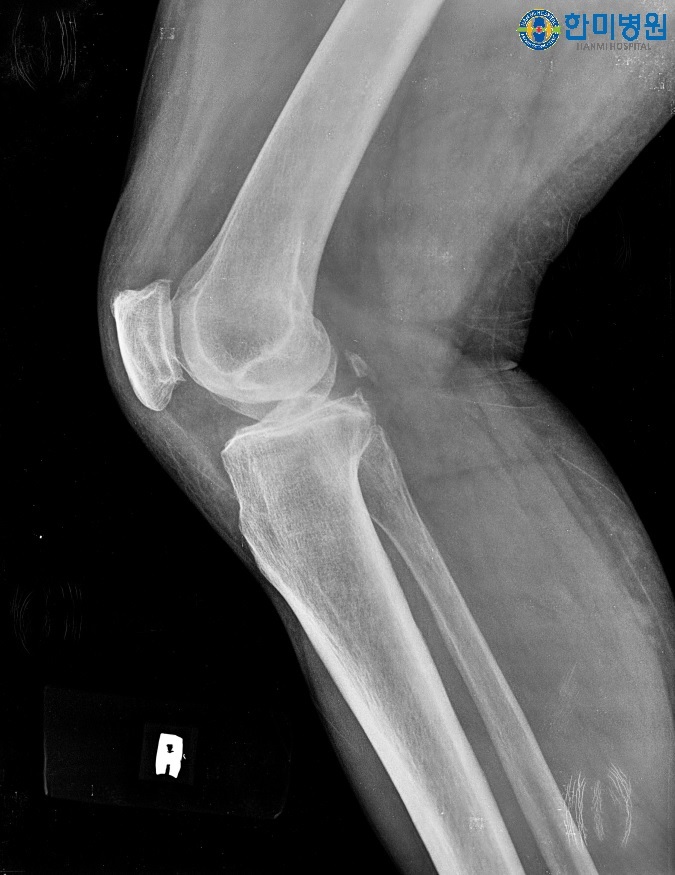

[무릎인공관절 수술 전 사진]

환자명 : 권**님

나 이 : 82세

수 술 일 : 2017년 06월 왼쪽 무릎인공관절 수술

수술 병원 : 대구 정형외과 한미병원

방 문 일 : 2018년 05월

환우분 상태 및 안내 : 수술 후 여행을 다닐만큼 좋은상태이며 오래 걸어다녀도 문제 없다고 하심수술 부위 굴곡 140° 정도 수월하시고 양반다리도 가능하심

수술받지 않은 우측다리는 통증이 조금 있다고 하심

평소 걷기 운동을 부지런히 하시고 근력운동의 중요성을 잘 아시고 본인 스스로 열심히 운동을 하심